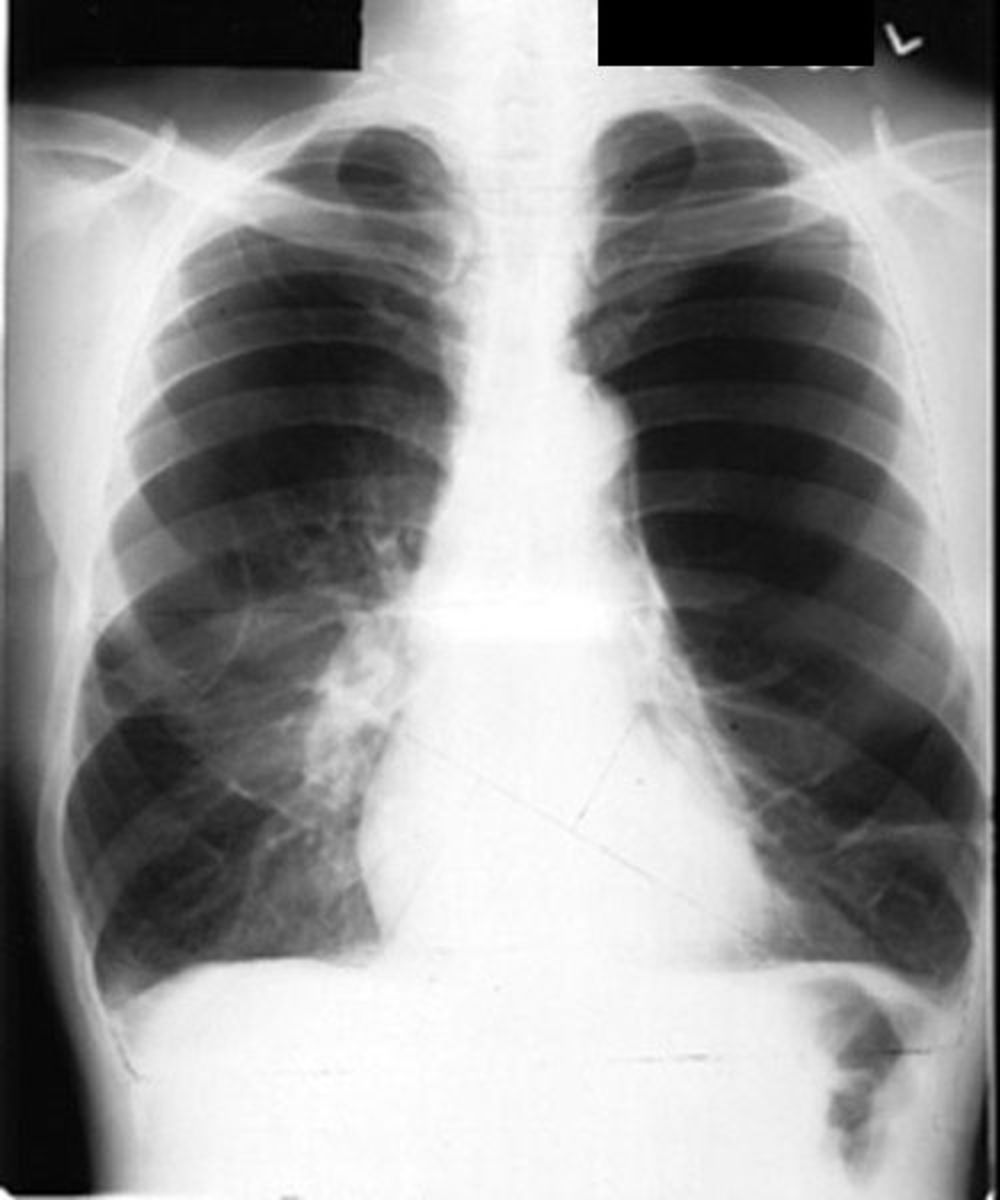

Chest radiograph showing increased bronchovascular markings with right Chronic Bronchitis Chest X Ray Results Imaging can show your provider if there’s any damage or areas of concern in your lungs. They’ll use a machine to take pictures of your heart and lungs. Plain chest radiography in chronic bronchitis. Chronic bronchitis most often results from overproduction and hypersecretion of mucus by goblet cells. A culture of the sputum when a bacterial infection is suspected is. Chronic Bronchitis Chest X Ray Results.

Chronic Bronchitis Chest X Ray Results . A culture of the sputum when a bacterial infection is suspected is indicated. Most common findings in ct were thickening of bronchial walls (64%), intralobular micronodules (61%) and septal thickening. Imaging can show your provider if there’s any damage or areas of concern in your lungs. Generally, chest x ray is not recommended for chronic bronchitis diagnosis, but it is common to order it to rule out other causes of dyspnea and. Chronic bronchitis most often results from overproduction and hypersecretion of mucus by goblet cells. In the absence of accompanying emphysema and hyperinflation, the majority of. They’ll use a machine to take pictures of your heart and lungs. Plain chest radiography in chronic bronchitis.